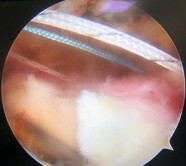

- Tiến hành buộc nút chỉ mũi khâu nằm ngang trước, đảm bảo sao cho sợi chỉ của mũi khâu dọc nằm phía trên nút chỉ của mũi khâu nằm ngang. Tiếp đến buộc nút chỉ của mũi khâu dọc còn lại.

Hình 2.26. Buộc mũi chỉ dọc sau khi buộc mũi chỉ nằm ngang và hình ảnh sau buộc chỉ

* Nguồn: ảnh chụp trong mổ của BN Trần Hồng Ph, mã số bệnh án

19057840